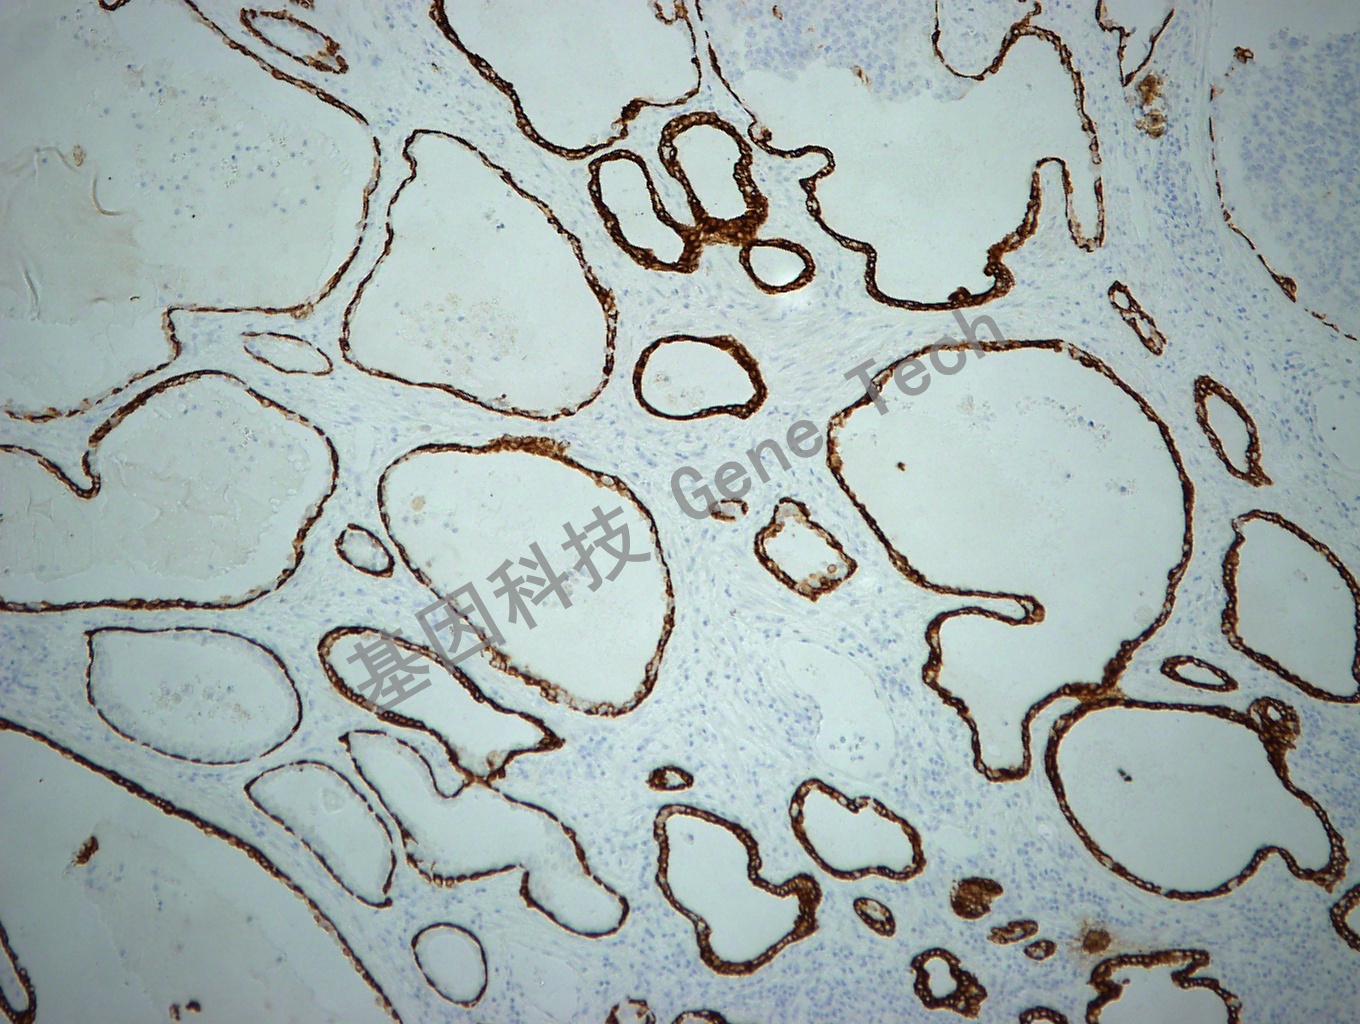

前列腺增生石蜡切片,用 CK,HMW(GM0630)染色,细胞浆阳性,DAB 显色。(40×)